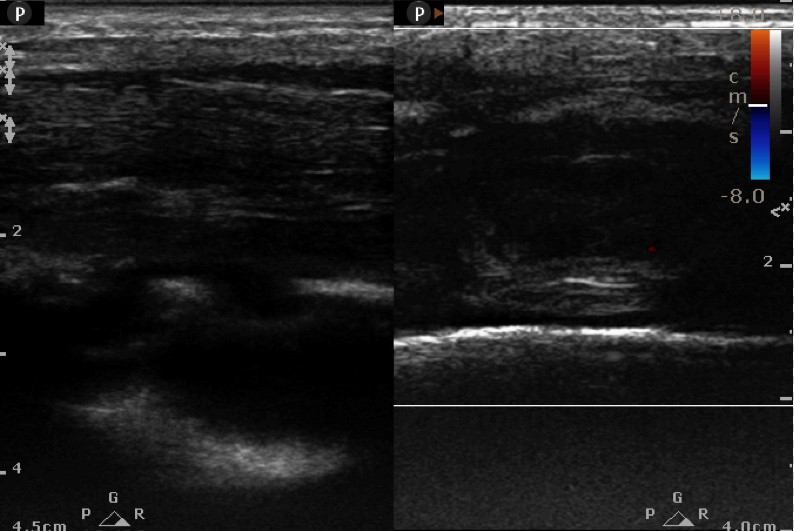

High frequency Ultrasound ( L12-5 MHz) (within 10 minutes of patient skigram): Increased thickness of belly of triceps. On CDU, increase vascularity. Cortical breach as punched - out (*)erosive lesion measuring 4x3 mm in mid shaft posterolateral humerus with new bone formation(^) . No periosteal or juxta cortical fluid.

Ultrasound provisional Diagnosis: Fibroscarcoma. Advised Ultrasound guided Tissue Biopsy.